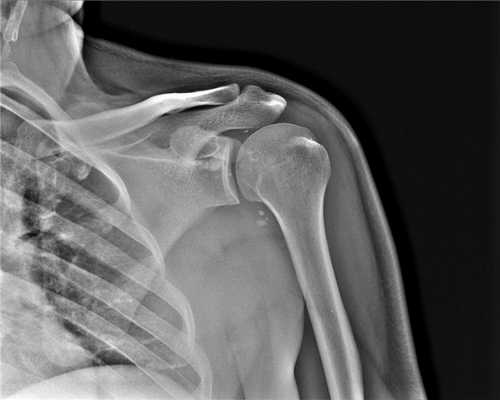

Рентгенография, хотя и не позволяет выявлять разрывы связок и суставной губы, остаётся обязательным диагностическим методом при травме плечевого сустава. Она позволяет обнаруживать переломы и костные дефекты, смещения, свободные фрагменты.

На КТ хорошо видны костные дефекты и дефекты гиалинового хряща суставной впадины. Гиалиновый хрящ, покрывающий головку плечевой кости виден гораздо хуже.

КТ плечевого сустава, Переломы Банкарта и Хилла-Сакса.